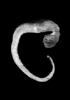

Carnegie Stage 14 (32 post-ovulatory days)

Most embryos at stage 14 are approximately 32 postovulatory days old and measure 5-7 mm in length. Distinguishing criteria for this stage include an open lens pit with invagination of the lens disc and elongated and tapering upper limb buds. The otic vesicle with a well-defined endolymphatic appendage is also a hallmark of this stage.

Animations